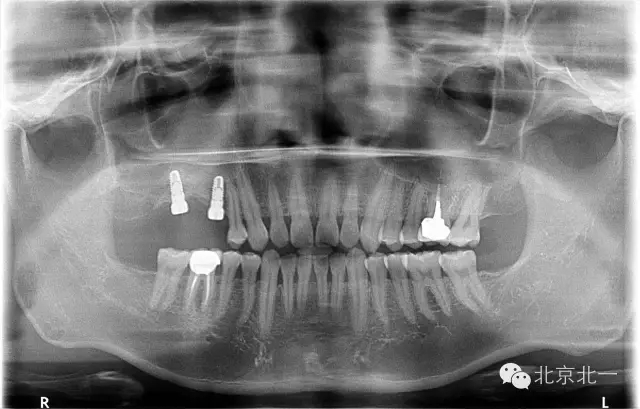

患者,男,30歲,右側(cè)上頜后牙區(qū)缺失,咨詢種植。

檢查:15、16 缺失。17三度松動。

圖二:手術(shù)前全景片